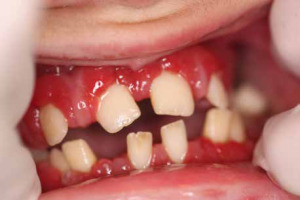

When he was 5 years of age the intraoral examination revealed incomplete primary dentition with five missing teeth, marginal gingivitis, interdental papilla hypertrophy, carious lesions in seven primary teeth, and one permanent tooth of various degrees of advancement for conservative treatment (Fig. 1). The patient was qualified for simultaneous dental treatment under general anesthesia. A panoramic radiograph picture was taken showing the advanced destruction of the alveolar bone in the maxilla and the alveolar part of the mandible. Three primary teeth were completely devoid of bone base. The roots of the lower incisors were only half of their normal length (Fig. 2). Under antibiotic protection (amoxicillin with clavulanic acid at a dose of 30 mg/kg), professional removal of dental plaque and conservative treatment of teeth extraction of four primary teeth with complicated caries and periodontitis were performed. The patient was provided with permanent dental care.